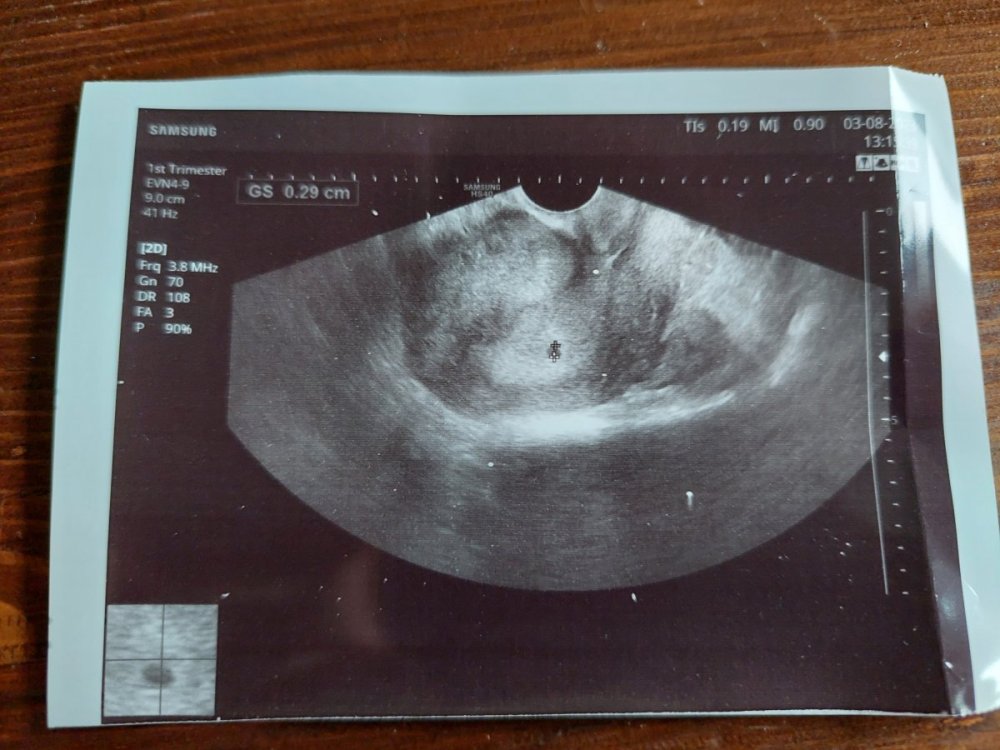

Jestem po wizycie, jest pęcherzyk 2,9 mm, 4+4, czyli wszystko ok. Powiedzialam gince, że mnie potwornie wystraszyła, tyle razy mówiła o ciąży ektopowej. -